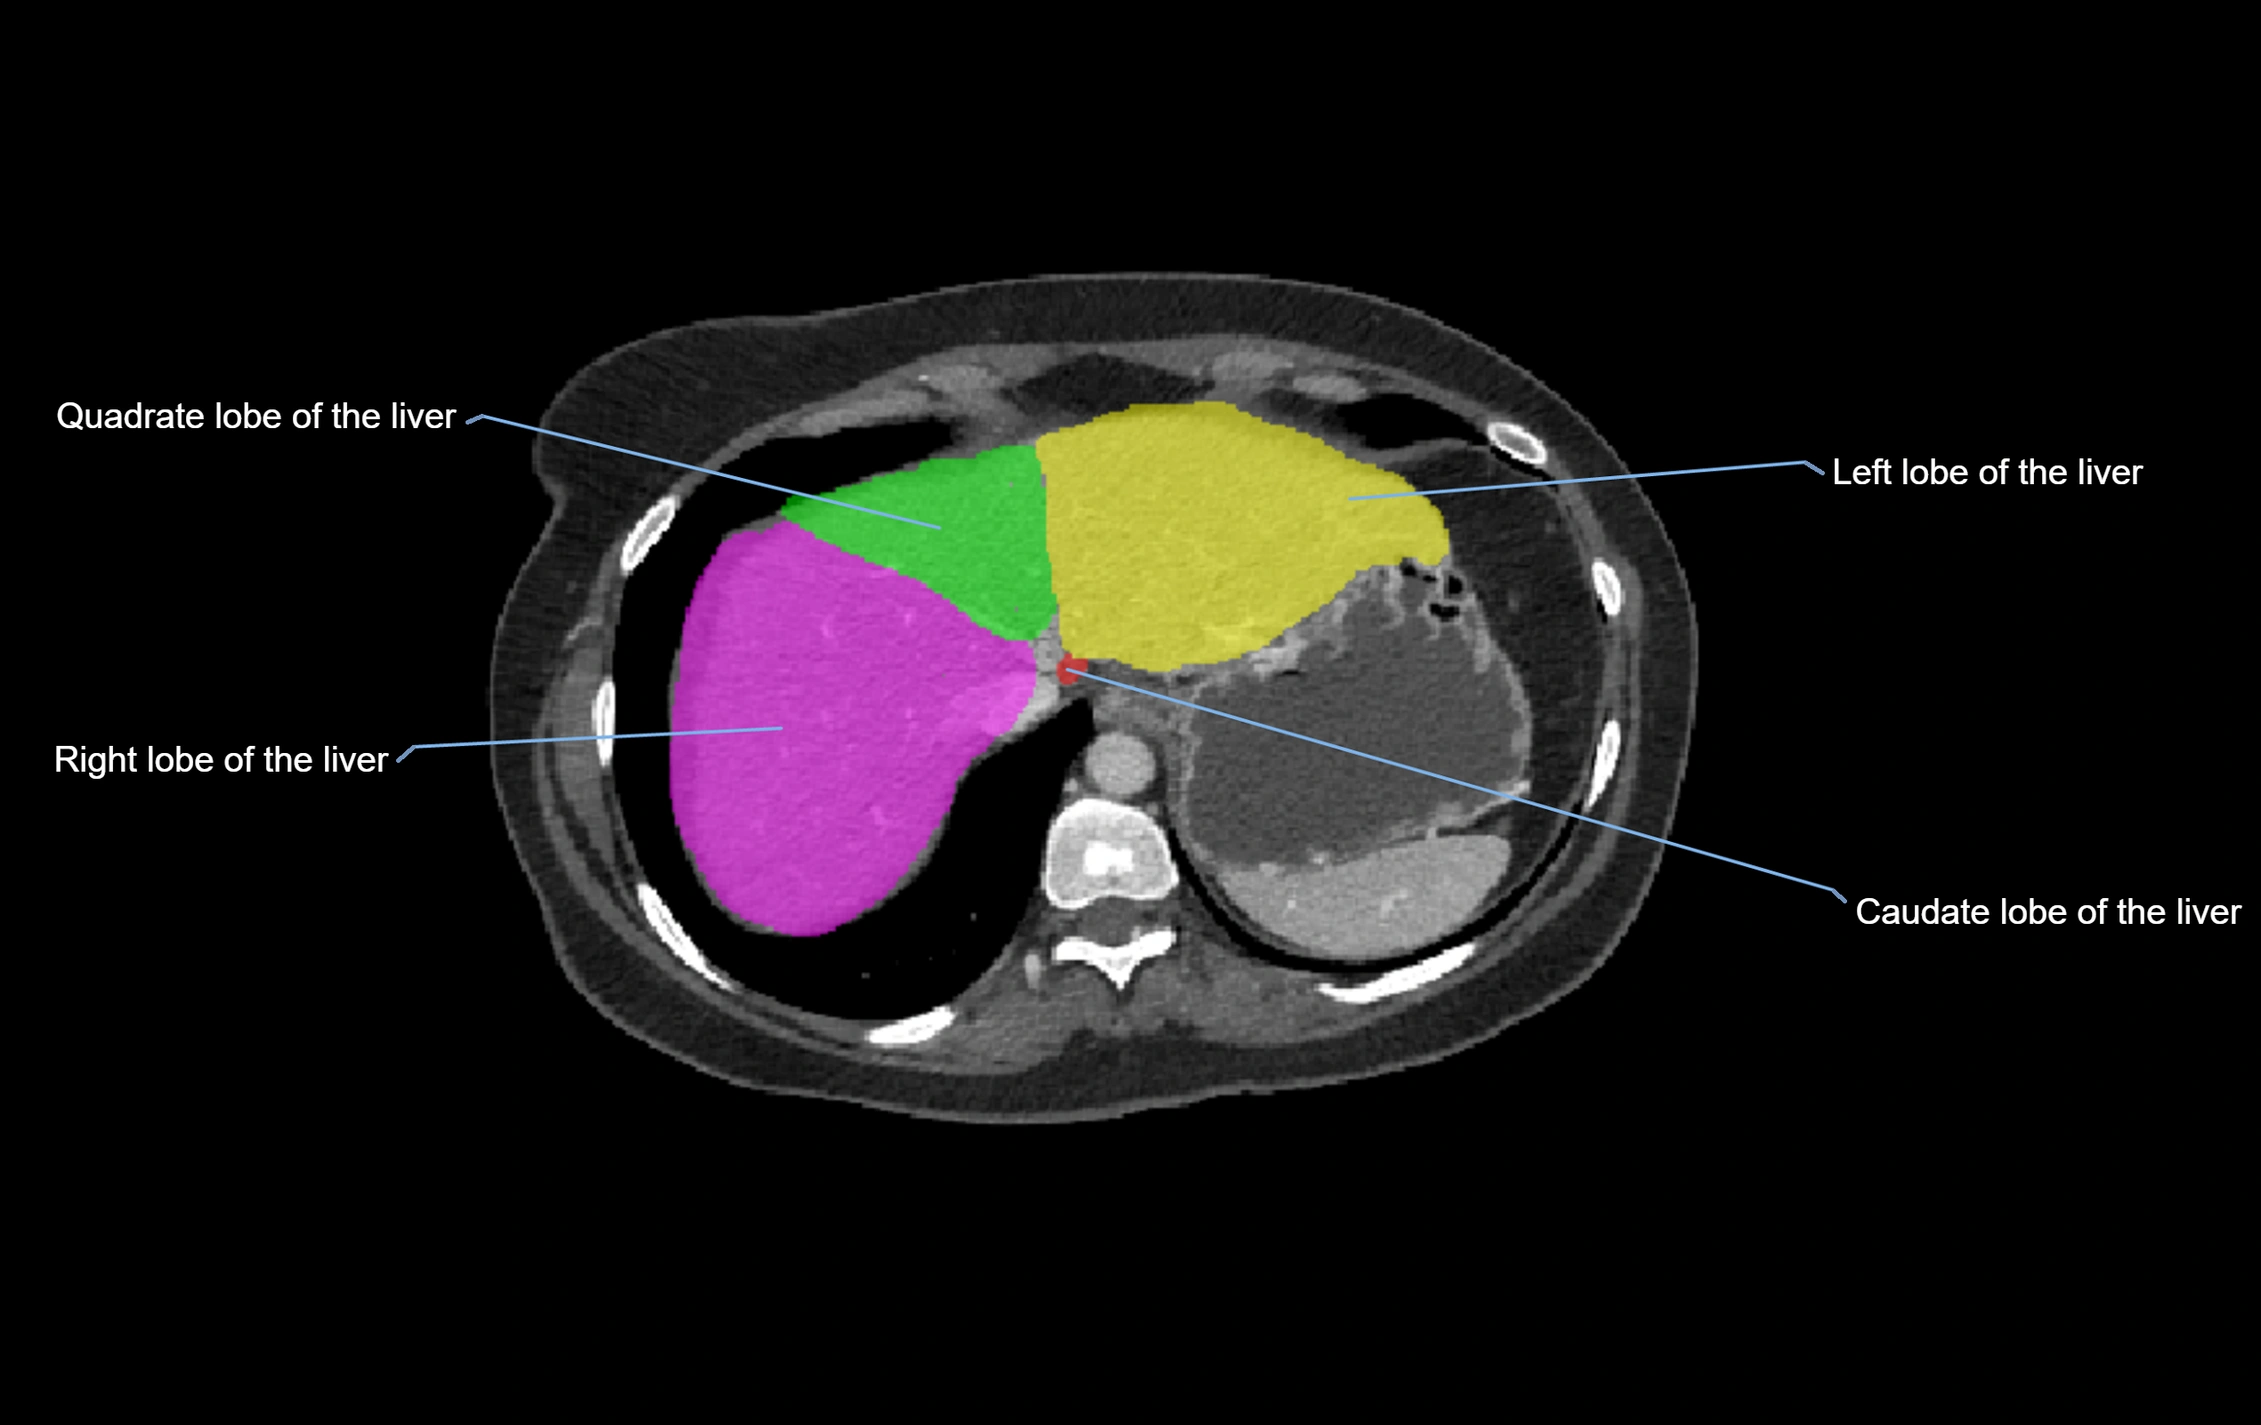

CT Appearance

CT Pre-Contrast:

• Caudate lobe appears as a soft-tissue density, isodense to the rest of the liver

• Enlargement may be appreciated in cirrhosis or Budd–Chiari syndrome

CT Post-Contrast:

• Homogeneous enhancement in the portal venous phase, similar to rest of liver

• Independent venous drainage into the IVC may be visualized

• Lesions follow characteristic CT enhancement patterns (HCC: arterial hyperenhancement with washout; hemangiomas: peripheral nodular enhancement with centripetal fill-in)

CT Venous Phase (functional significance):

• Caudate lobe often enhances relatively more than other lobes in Budd–Chiari syndrome, due to preserved venous outflow

CT Image

image